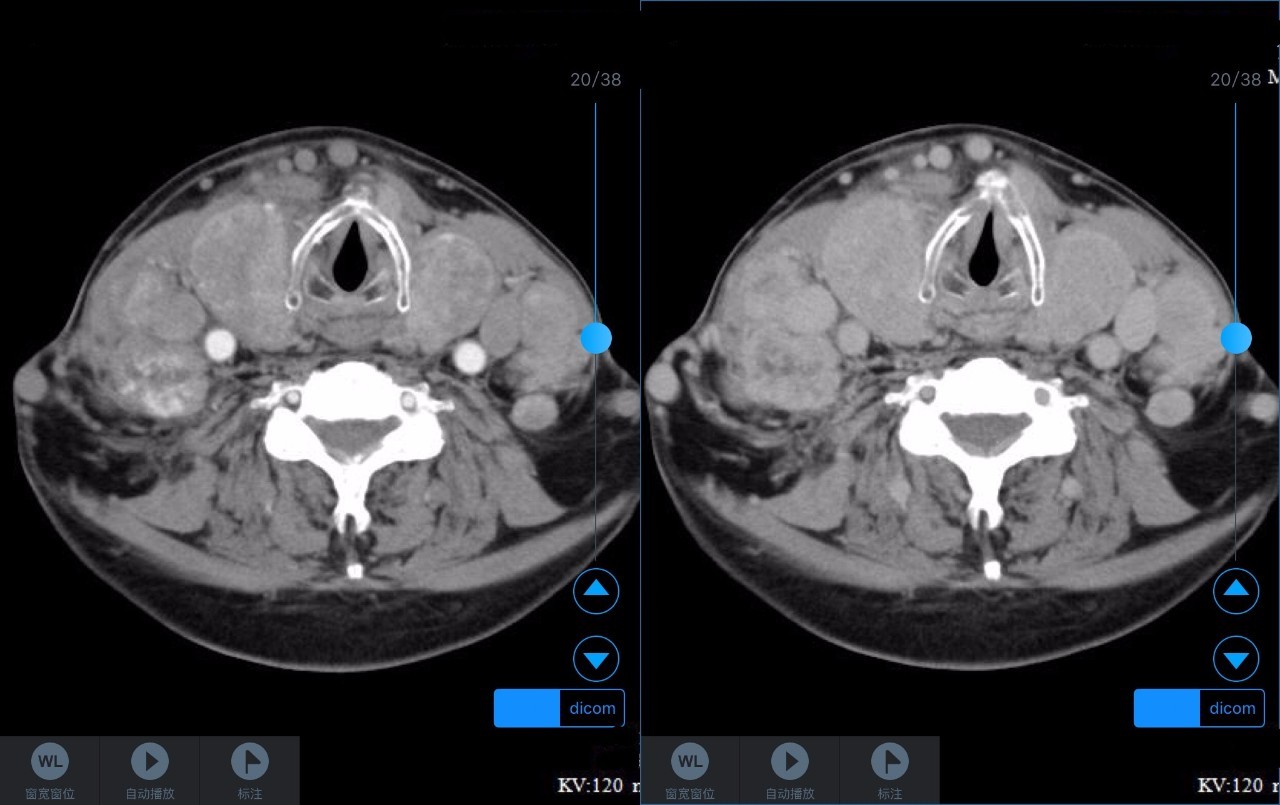

▼患者CT平扫(右)及增强CT(左)检查报告资料

Z主任 甲状腺肿大,内见弥漫多发结节,界限不清,甲状腺包膜毛糙。双侧颈部、锁骨上、纵隔多发肿大淋巴结,病变均强化明显,密度不均,边缘毛糙,考虑甲状腺恶性肿瘤伴多发淋巴结转移,或甲状腺内也是转移瘤。Castleman病多灶者少见,一般病变边缘光整,也不会累及甲状腺。建议穿刺活检。 C主任 双侧甲状腺肿大,密度不均,不均匀强化,甲状软骨未见明显骨质破坏气管右侧壁受压;双侧颈部多发肿大淋巴结,不均匀强化;考虑为甲状腺恶性占位性病变伴双侧颈部淋巴结转移,建议组织学进一步检查。 声明:以上资料均来自和缓名医平台的真实案例,为保护用户隐私,均用化名代替。资深医师Z咨询反馈